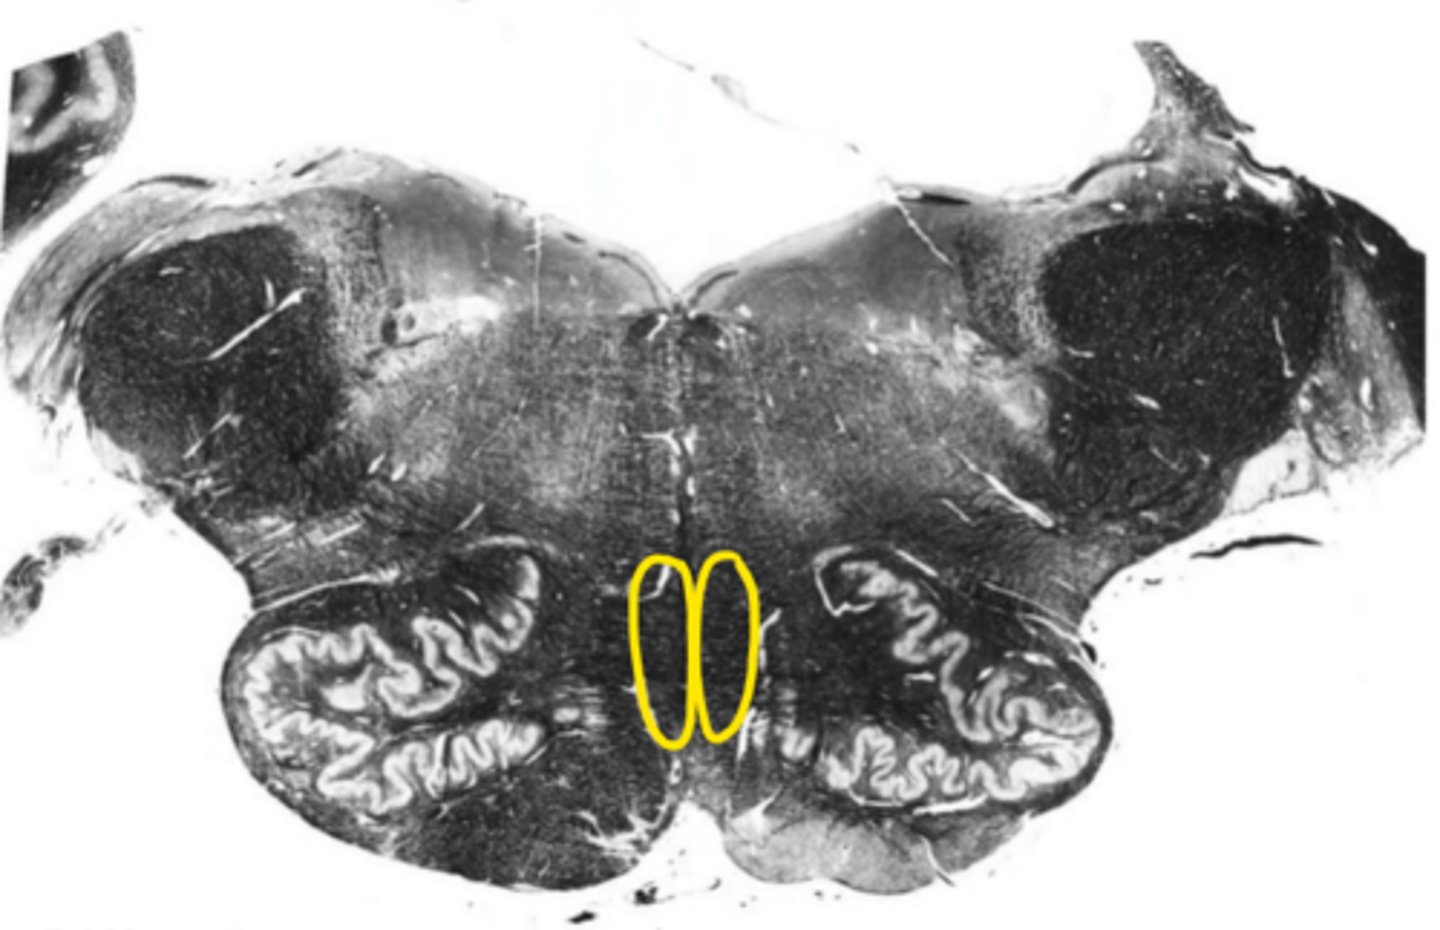

central canal

ID the space

open medulla

ID the brainstem level